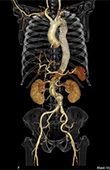

・3D(三次元立体)画像

大動脈

CT(Computed Tomography:コンピュータ断層撮影)検査とは、体の周囲からX線を照射することによって断層(輪切り)像が得られる検査です。 CT検査の特徴として、通常のX線撮影などで検出されにくい小さな病変を見つけることができ、広範囲な撮影も可能です。造影剤を用いる事により血管の狭窄や閉塞、瘤の存在や形態を把握できます。また、タイミングを変えて(多時相)撮影することで、腫瘍の良悪性や広がりなどを詳しく調べる事ができます。薄いスライスの画像を重ね合わせて得られる3D(三次元立体)画像は、病変部と血管また骨などの位置関係を多方向から容易に把握できるので、診断や治療等へ活用されています。

当院のCT装置はSOMATOM Force (SIEMENS社製)及び 、Optima CT660 Pro (GE社製)の2台が稼動しており、通常は予約検査で行っておりますが、当日や緊急検査にも対応しています。肺がんを早期発見する為の肺検診では胸部CT検診学会の基準に則った低線量 (X線)で撮影しています。また、心疾患の診断、肺病変の性状を調べる為の肺生検、メタボリックシンドロームの指標となっている内臓脂肪量測定検査なども行っております。